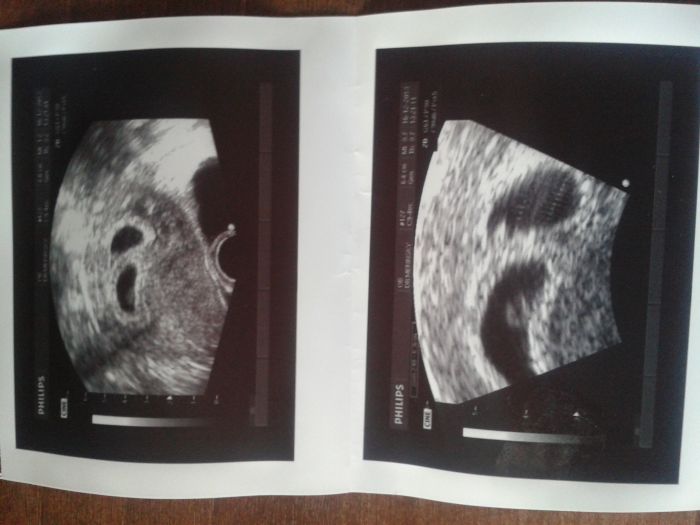

A vítám Nikiku!!!! Držím palce, ten UZ vypadá dost čerstvě, tak držím palce ať nejsou začátky moc dramatické, aby to byli dva malí Ježíšci, nebo andílci,... Ono je to vlastně stejné jako s jedním dítětem, co se týče vyšetření, jenom někteří doktoři tě chtějí vidět častěji než s jedním dítětem. Ono je to spíš potom rozdíl když ten pupek vyroste, vyroste daleko dřív než s jedním a to pořádně. Já tedy nevím jak ostatní holky, ale jak píší, začínám 3.trimestr a cítím se jak před porodem s prvním jedním dítětem. I co se nabraných kil týče, ale to je zase - bohužel.- individuální., Já jsem prostě matka pluku se vším všudy, i s tou váhou :-D Ještě že se umím sama sobě zasmát, jinak bych už plakala!!!!